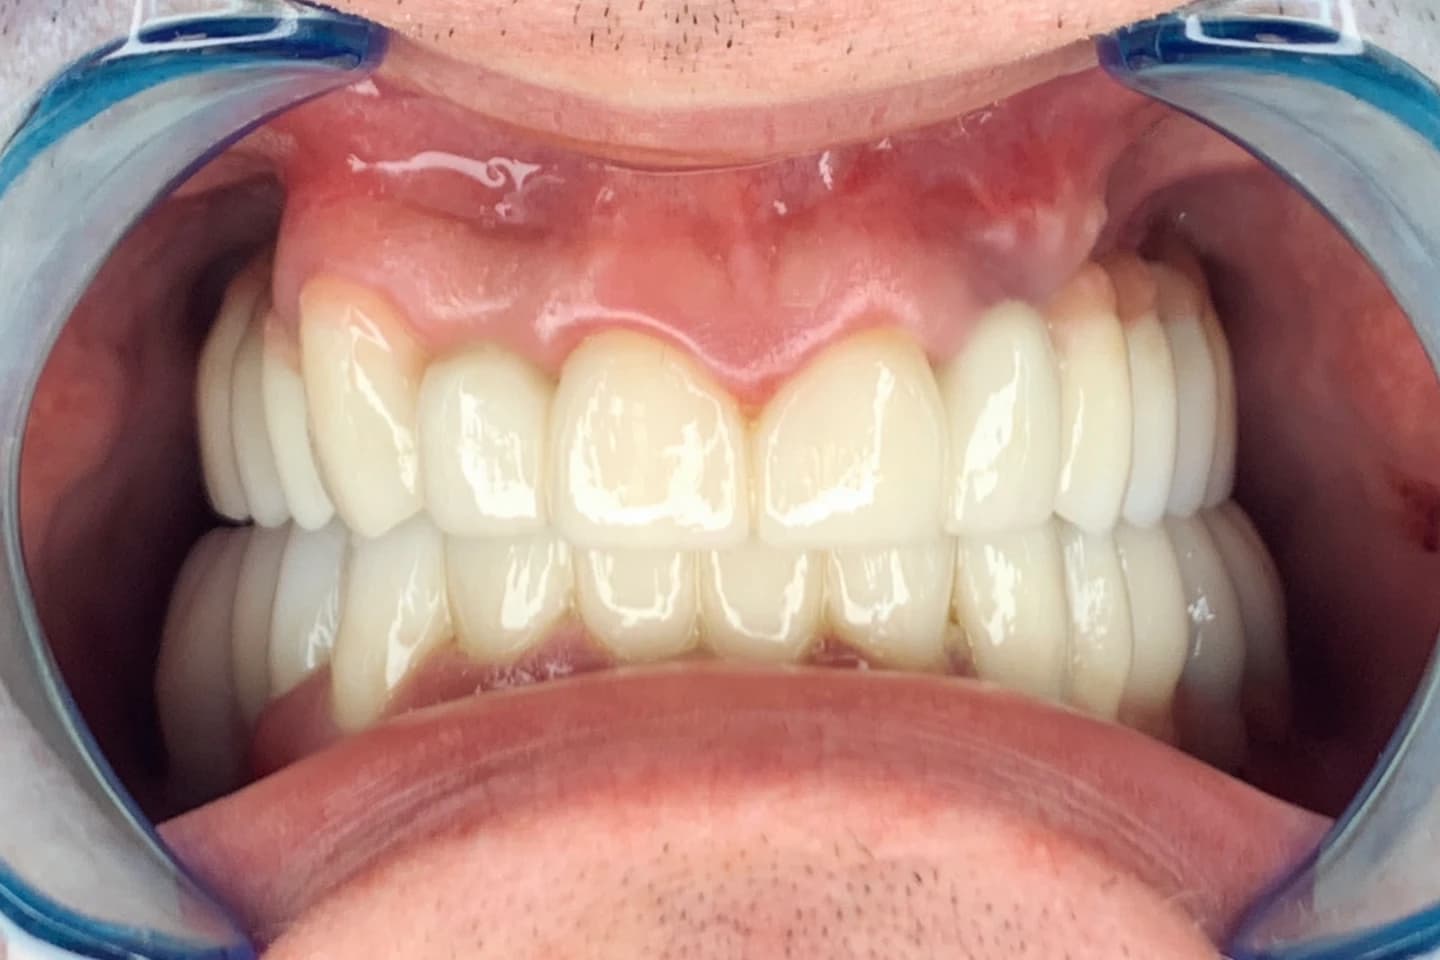

Krunice za zube - pre i posle

- Pogledajte kako krunice mogu da zaštite i obnove oštećenost kada su u pitanju zubi, vraćajući im estetiku i funkciju. Galerija radova će vas inspirisati da i vi transformišete svoj osmeh.